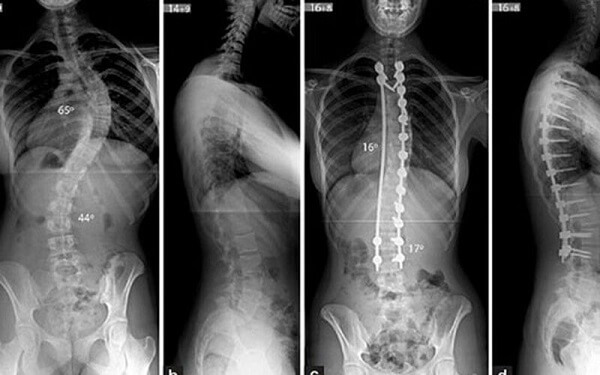

Người bệnh cũng được chỉ định chụp lại tình trạng cụ thể, phổ biến nhất là chụp X- quang để đánh giá cấu trúc cũng như phần cứng, lỗ hẹp liên hợp; Chụp CT để nắm sâu hơn về cấu trúc xương, chẩn đoán lao và u cột sống.

- Thay đổi độ cong của cột sống: Khi đường cong sinh lý của cột sống bị biến dạng diễn ra trong thời gian dài mà không được điều chỉnh sẽ gây ra tình trạng mất thăng bằng cho cơ, các dây chằng, đĩa đệm. Người bệnh có thể bị cong vẹo cột sống vĩnh viễn; Không chỉ cột sống cong lệch sang 1 bên mà còn xảy ra các cơn đau nhức dai dẳng, gây khó khăn trong sinh hoạt.